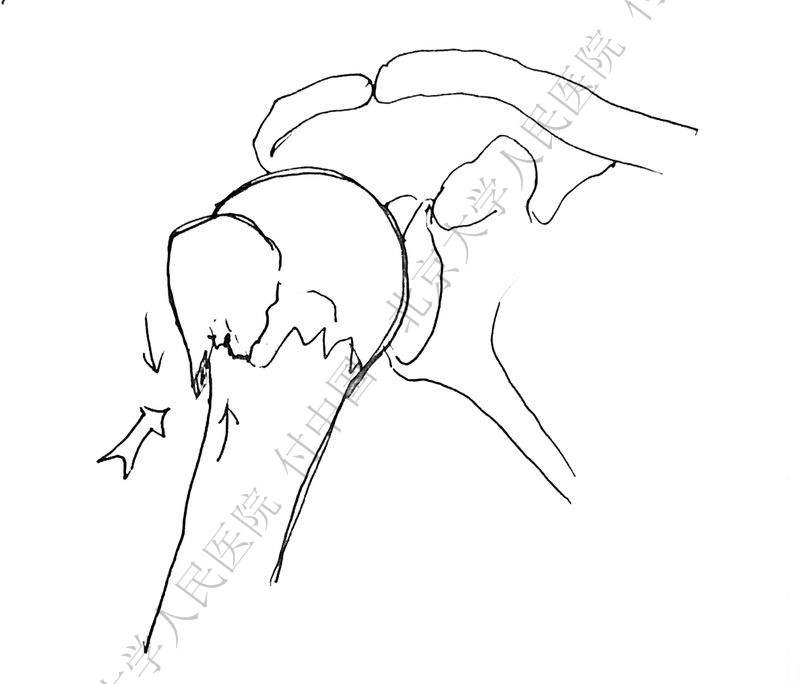

警惕孤立性向下移位的大结节骨折

外翻压缩型肱骨近端骨折

X线是孤立性向下移位的大结节,一定要小心,多伴有肱骨外科颈骨折